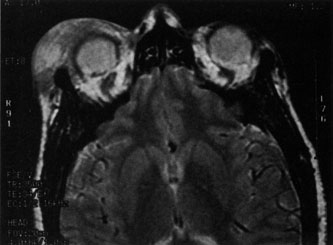

Magnetic resonance imaging (MRI) is purported to be more useful than CT in the diagnosis of preseptal cellulitis. It is less reliable at diagnosing the subtle signs of muscle enlargement and periscleritis and thus is not as useful in differentiating orbital cellulitis from other inflammatory orbital diseases.71 On MRI with gadolinium contrast, orbital cellulitis may show a smearing or linear streaking of the normal fat shadows on T2-weighted images. MRI is excellent for demonstrating localized fluid collections such as abscesses. It is not helpful in distinguishing a transudate from an exudate, because both appear liquid and are of low intensity on T1-weighted images and bright on T2-weighted images (Fig. 19).

Fig. 19. Magnetic resonance image of preseptal cellulitis with anterior abscess formation.

MRI is superior to CT in the diagnosis of cavernous sinus thrombosis. T2- and proton-weighted images show high signal luminal narrowing as well as absent flow or localized parenchymal infarcts (Fig. 20).72 Absent flow can be demonstrated as well in the superior ophthalmic vein in cases of carotid or cavernous sinus thrombosis.72 MRI with gadolinium can help define these abnormalities and can detect dural invasion.

Fig. 20. Cavernous sinus thrombosis. Axial T1 image shows cavernous carotid luminal narrowing on right and enlargement of right cavernous sinus. Note extensive sinus disease.

MRI may be helpful in distinguishing orbital inflammatory diseases such as orbital pseudotumor from orbital cellulitis.73 MRI is most helpful in distinguishing the diffuse orbital form of orbital pseudotumor as well as the localized inflammatory pseudotumors such as the myositis, periscleritis, and scleritis forms. The diffuse orbital form is most commonly seen on MRI as a reticular pattern with isointense signals in the orbital fat in both T1- and T2-weighted studies.73 Orbital cellulitis is best characterized by a diffuse pattern that is isointense in T1-weighted images and hyperintense on T2-weighted images.73